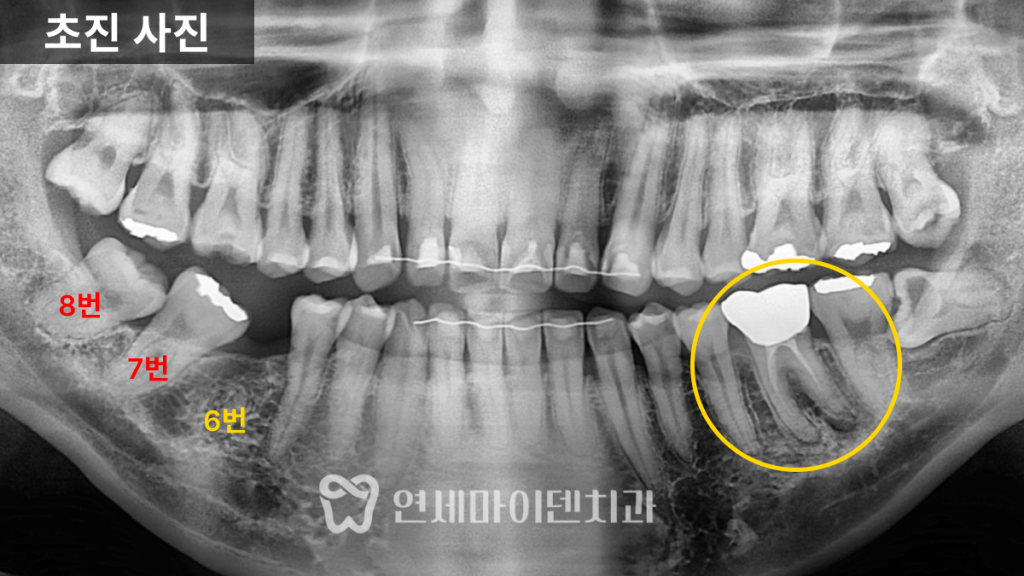

임플란트 공간이 부족했던 초기 상태

해당 환자분은 오른쪽 아래 6번 어금니를

오래전에 발치하신 분으로,

그 결과 뒤쪽의 7번 어금니와 8번 사랑니가

앞으로 기울어져 있었습니다.

이로 인해 임플란트를 식립할 공간이 부족한 상태였고,

보철만으로는 치료가 불가능했습니다.

파노라마 사진을 통해 확인한 결과,

- 6번 치아 부위의 공간이 심하게 좁아져 있었으며

- 위아래 사랑니는 모두 자라 있었고, 일부는 충치가 심했습니다.

특히 오른쪽 아래 사랑니(8번)는

앞 어금니를 제자리로 되돌리는 데 방해가 되어,

공간 확보를 위해 사랑니 발치 후

부분교정 치료를 진행하기로 하였습니다.